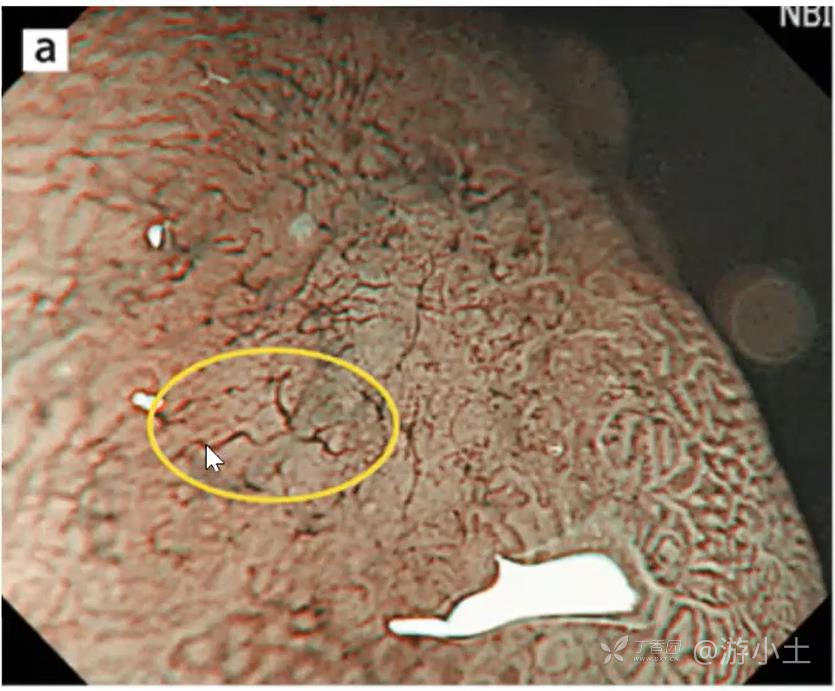

1、血管粗细的不同:指血管纹理突然变粗活变细,血管直径变化往往在2倍以上(见图a);

2、血管走形不规则:指血管的走形和分叉不规则(见图b);

3、有无形成血管网:血管的封闭曲线,追踪血管走形后回到原始位置的为网格状(见图C),不形成封闭曲线,向侧方分叉扩展的判断为非网格状(图),这一点是最重要的。